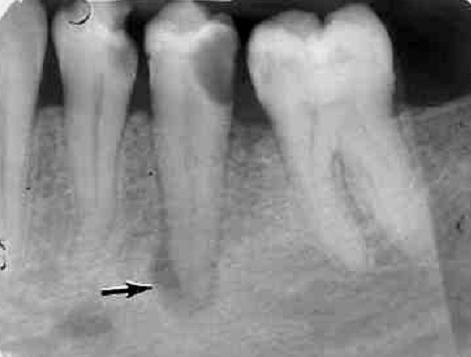

Периапикальный абсцесс мкб